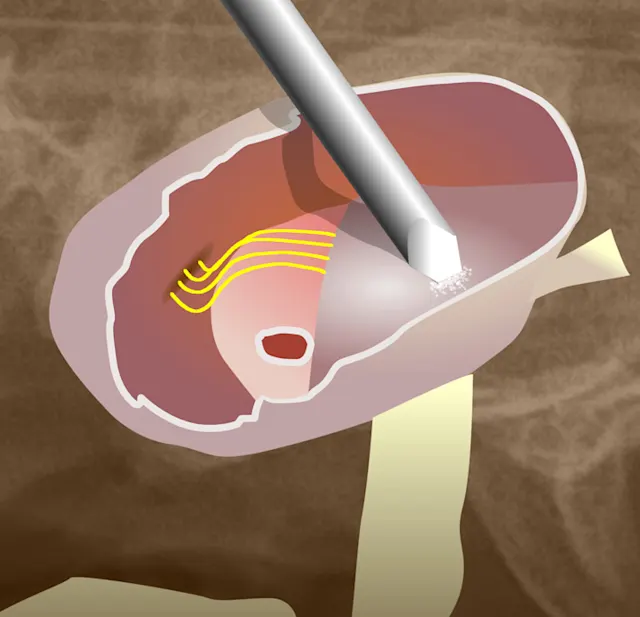

On the Cutting Edge

A CO2 laser can destroy remnants of the polyp in the middle ear via an aural approach. However, no studies have been published on the efficacy of this technique or any associated side effects.